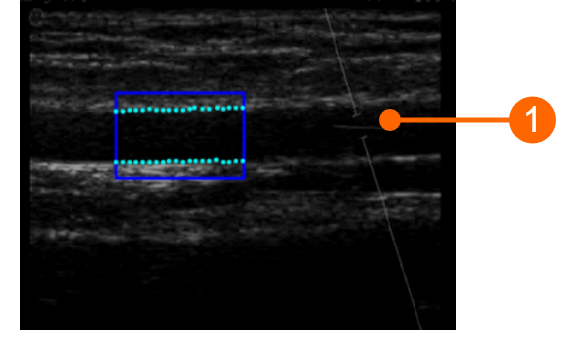

The angle between the Doppler beam and the vessel orientation should be ≤60 degrees. The sample volume should be as wide as possible but without encompassing the vessel walls and allowing for a slight margin for error in case of movement. Pay attention that the cursor of the doppler sample volume is not into the ROI where the diameter is computed. It is recommended that the sample volume is 5 - 15 mm apart from the ROI.

images/download/attachments/381258618/cvs_setupDuplex_bmode_gliffy-version-1-modificationdate-1759328517224-api-v2.png

CAUTION: pay attention that nothing but the ultrasound image is into the ROI. Please note that the processing can be affected by annotations or any other graphical object that is superimposed to the image. In particular, pay attention that the cursor of the doppler sample volume is not into the ROI.